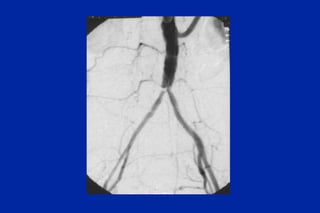

Este documento resume los principales tipos y técnicas de angiografía. Describe brevemente la angiografía, arteriografía, flebografía y linfografía, así como las técnicas de contraste y materiales utilizados. También explica los principales accesos vasculares, la técnica de Seldinger, la angiografía por sustracción digital y algunas técnicas endovasculares comunes.